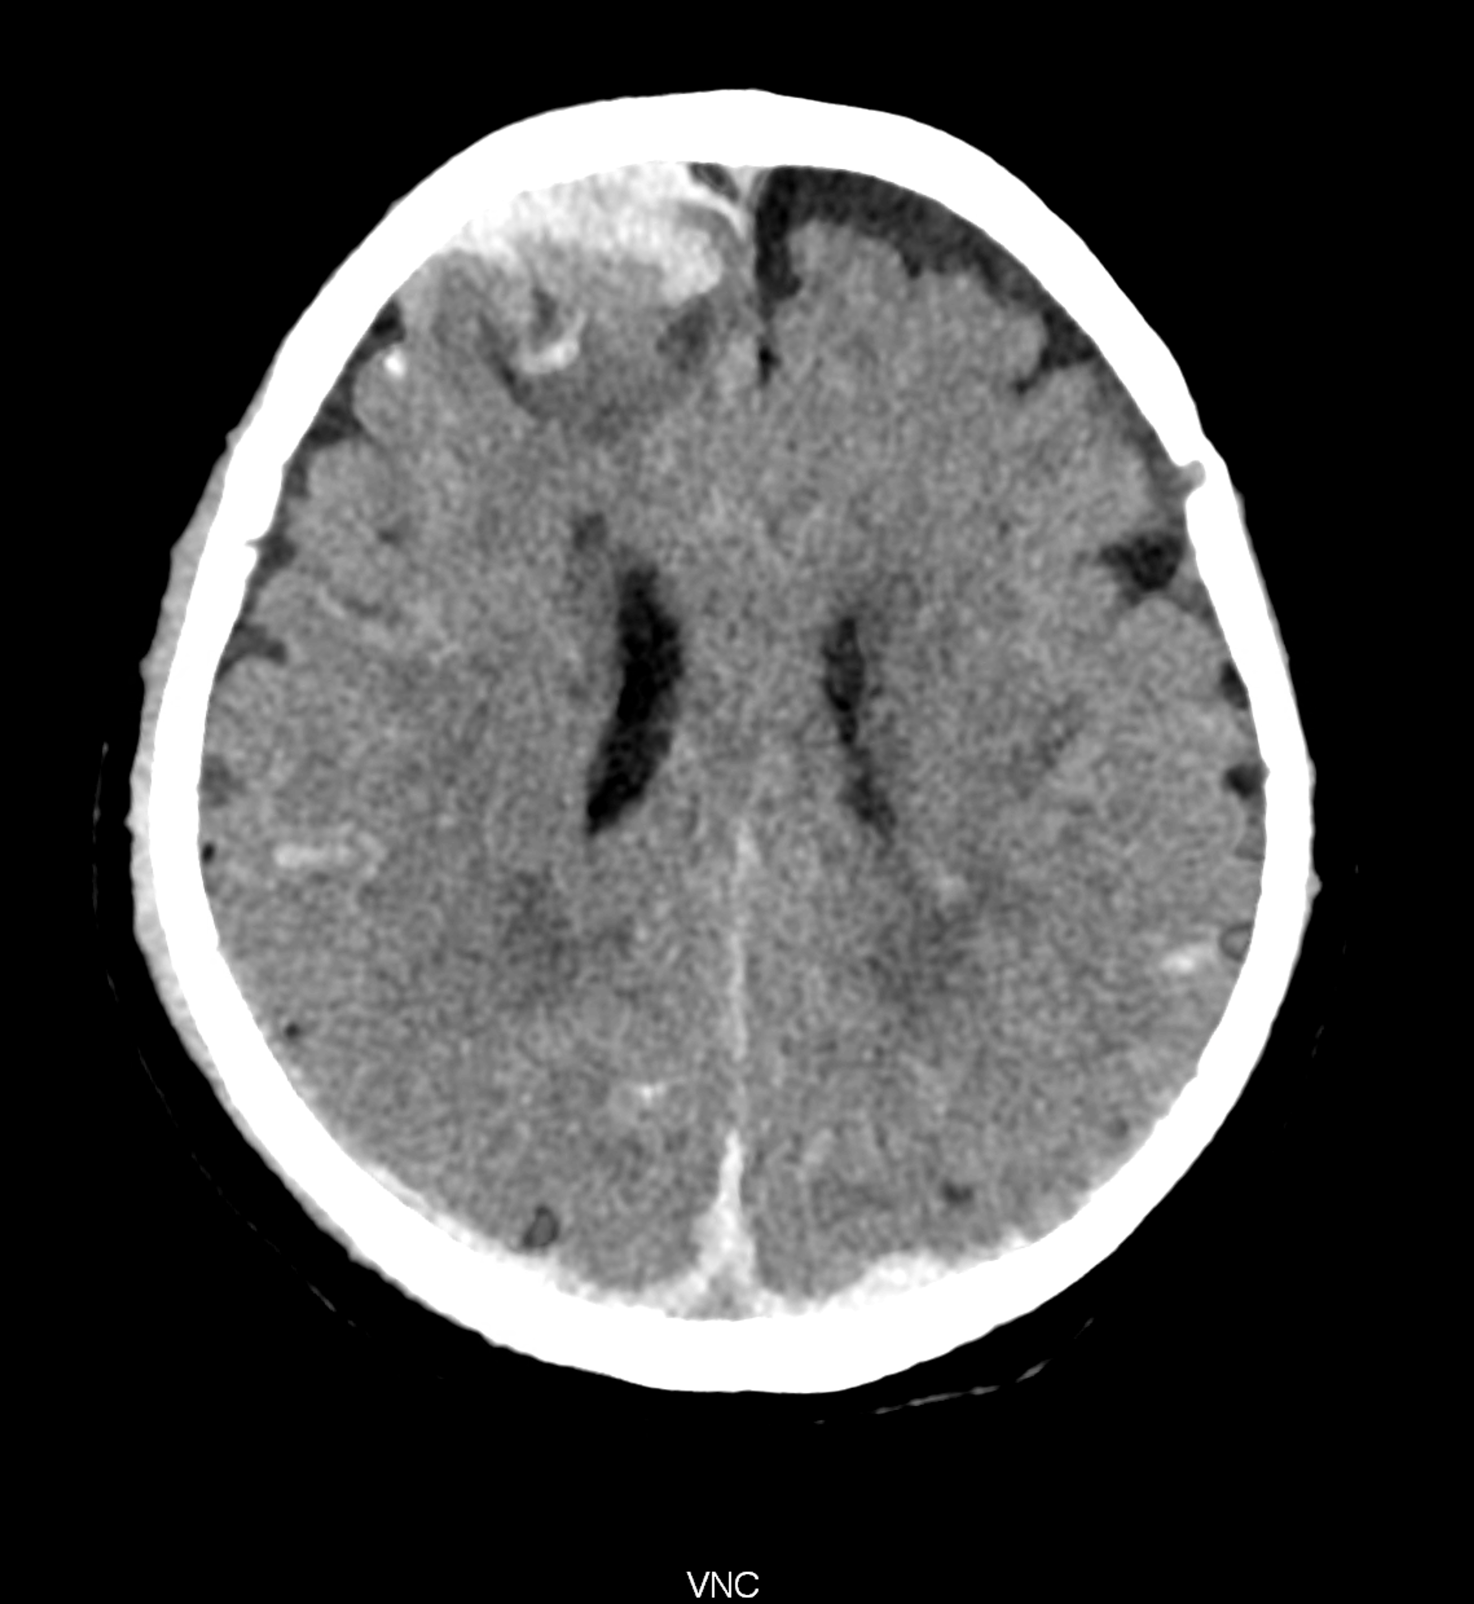

An example of the use of spectral imaging in complex brain injury, where contusions, diffuse axonal injury, subarachnoid hemorrhage, subdural hemorrhage, and blood in the ventricular system are present.

comparison of the images with the energies of monoenergetic reconstructions 40 keV, 67 keV (standard conventional reconstruction), 190 keV and virtual non contrast (VNC)